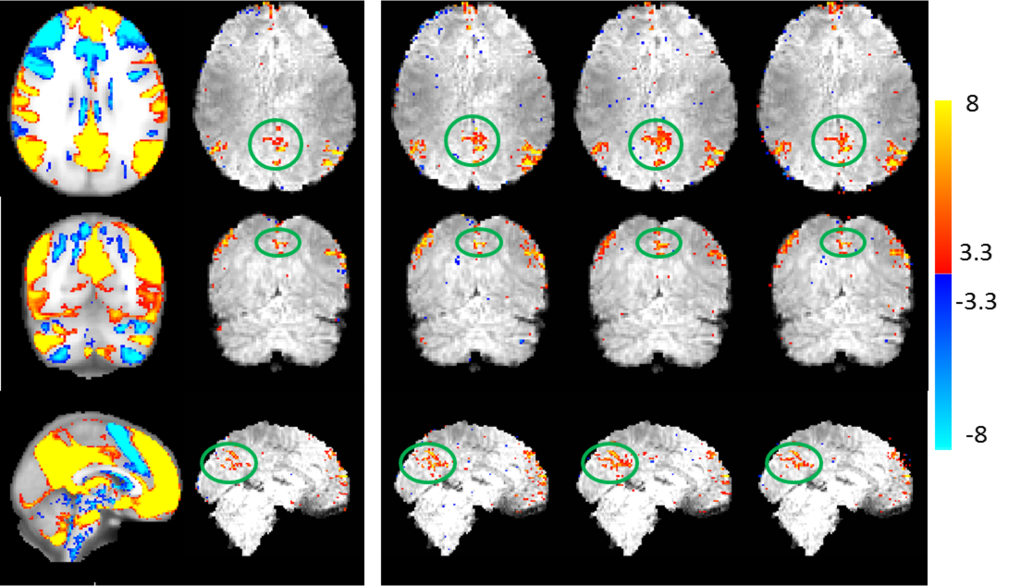

To examine the correspondence of the reconstruction with the ground-truth, we performed regression against the original timecourses using General Linear Model (GLM)Jenkinson et al. [2012]. Figure 3 shows the F-test results as null-corrected z-statistics mapsBeckmann et al. [2005], for the ground-truth data (fully sampled image without the addition of noise), L+S, k-t FASTER and PEAR, for both R=8 and R=16. All maps are thresholded at and shown with color scale mapped between .

It can be seen that PEAR provides the most reliable result, being the only method that almost perfectly recovers both “M” and “B” with minimum false positive errors at R=16. In addition, we see that L+S is unable to recover the aperiodic timecourse “R”, as opposed to both k-t FASTER and PEAR thanks to their fixed-rank component.

An interesting analysis is the contribution of each component in PEAR. Figure 4 shows the GLM results for the A and P components of PEAR separately (for R=16), where the z-statistics maps are thresholded at and shown with color scale mapped between . Note that the sum of the null-corrected z-statistics maps of A and P is not equal to the z-statistics map of PEAR, due to the null-correction applied for each map, that depends with each map’s noise level. However, the separation of PEAR into periodic and fixed rank components is clearly demonstrated. The A component highly corresponds with the letter “R” which is a purely aperiodic timecourse, and with the letters “M” and “B” that include an aperiodic part. The P component highly corresponds to the letters “F” and “I” which are purely periodic timecourses, and to the letters “M” and “B” that include an periodic part. As demonstrated, this separation allows better modelling and leads to better recovery compared to k-t FASTER and L+S. Another analysis is presented in Fig. 5, where example portions of the mean timecourses from the five letter ROIs are shown for the ground truth, L+S, k-t FASTER and PEAR reconstruction results, including the timecourses for the A and P components of PEAR separately. The timecourses are shown in arbitrary units, to allow proper examination of their structure. It can be seen that as expected, L+S is limited in its ability to track the rapid changes that appear in the letter “R”. In addition, the P component of PEAR indeed contains the periodic part of the signal, and therefore exhibits high correspondence with letters that are fully periodic (“F” and “I”).

Figure 6 shows the General Linear Model (GLM) F-test Jenkinson et al. [2012] results as null-corrected z-statistics maps that were computed against the realistic time courses of all letters, for the ground-truth data (fully sampled image without the addition of noise), L+S, k-t FASTER and PEAR, for R=8 and R=16. All maps are thresholded at and shown with color scale mapped between .

In correspondence with experiment 1, for realistic timecourses we see that for R=8, both k-t FASTER and PEAR provide similar results that outperform L+S. For R=16, we see that PEAR provides cleaner results, as can be seen mainly when comparing the recovery of the letters “F” and “B”. It can also be seen that all methods are unable to recover “R” and “I” due to the high undersampling ratio. It can also be seen that “R” and “I” are the letters with the lowest Z values in the fully-sampled, ground truth data, due to their low energy in this experiment.